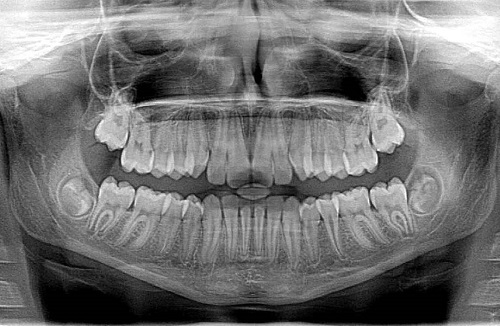

Then they took me out in the hallway and had me sit in a chair. They strapped my head to this thing and took what they called a panoramic X-Ray. The machine spins around in front of you and you have to hold still while it does its thing. It was weird.

The final result is something like this:

When the dentist finally came in to talk to me, I had been there an hour and a half. My teeth have never been straight. My two front teeth overlap and when I played trumpet in high school, I always played off to the side because of it.

He told me that my teeth look good “especially since it has been three years.” He suggested that my mouth would be healthier if I did something about the crooked and crowded teeth. Perhaps some of those Invisalign braces. I told him I would entertain the idea, but I know that it will cost me a pretty penny.

My teeth need a “deep cleaning” because of some bone loss. So I have to go not once, but twice! 90 minute visits! They will do one side on my first visit and the other on my next visit. While I am there for one of the visits, they will remove an old filling and put in a new one. I will need to be numbed up for both cleanings. URGH!!!